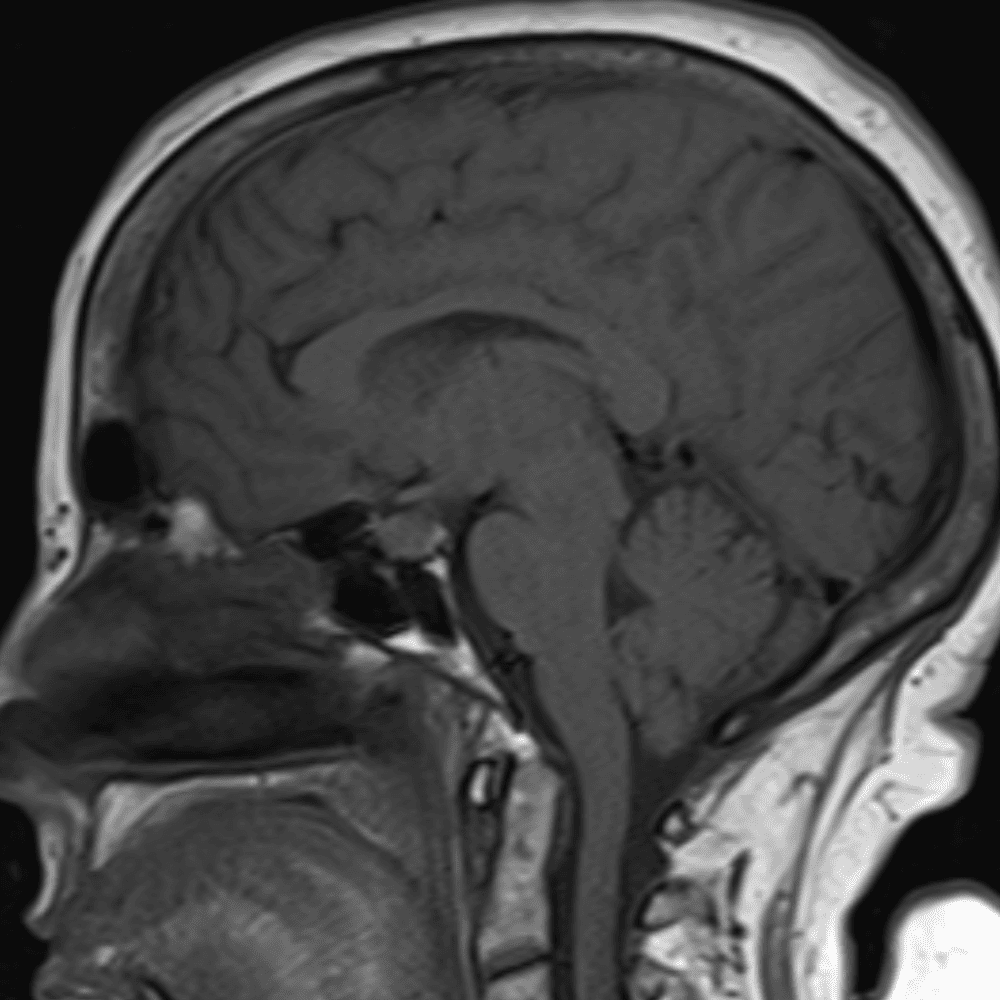

๋‹น์ง ์‹œ ํ”ํžˆ ๋ณผ ์ˆ˜ ์žˆ๋Š” ์‚ฌ๋ก€์˜ ์ „ํ˜•์ ์ธ ์˜ˆ๋ฅผ ํฌํ•จํ•ฉ๋‹ˆ๋‹ค.

39 ์‚ฌ๋ก€